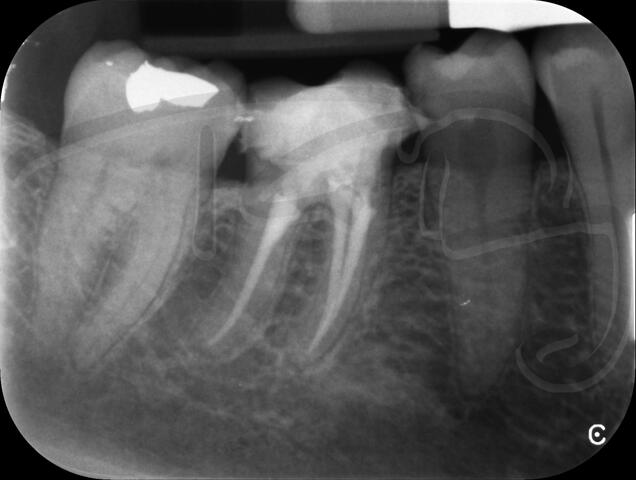

At the 2017 BDA Conference, Thomas spoke at two lectures about getting the best out of endodontic techniques and equipment.One of the main matters that he covered was understanding the causes of false positive and false negatives in the use of electronic apex locators.He described getting the best out of other methods of root canal length determination available.